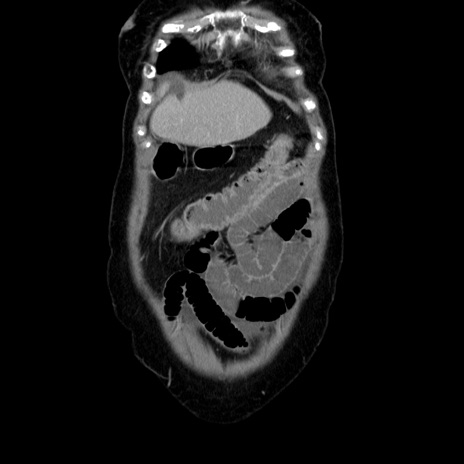

症例5(冠状断像)

【症例】70歳代女性

【主訴】お腹が張る

【現病歴】1週間くらい前から腹部膨満の自覚あり。昨日夜から増悪したため、本日救急外来受診。

【身体所見】意識清明、BT 36.5℃、BP 165/106mmHg、HR 80bpm、SpO2 98%、腹部:膨満、軟、自発痛・圧痛なし、触診にて不快感あり、腸蠕動音:減弱

【データ】WBC 12600、CRP 1.04